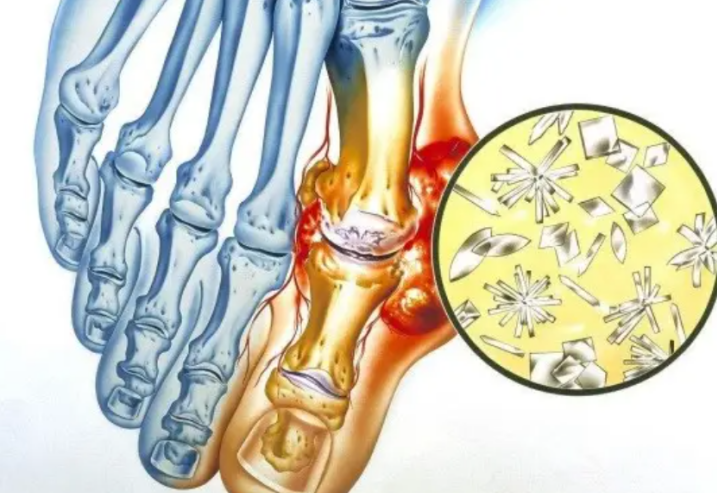

当人体的血尿酸含量过高 , 就会容易诱发痛风 。

每当痛风发作时 , 患者的关节就会又红又肿 ,

同时还会伴随剧烈的疼痛 , 对患者产生极大的折磨 。

特征二:痛风结石

除了剧烈的疼痛外 , 有些患者还会因为尿酸高 ,

而导致大量尿酸结晶堆积 , 体内长出痛风结石 。

虽然痛风结石 , 造成的疼痛并不严重;

但它却会不断侵犯周围组织 , 对骨膜和软骨组织造成损害 。

不仅影响关节活动 , 还会引发感染 。